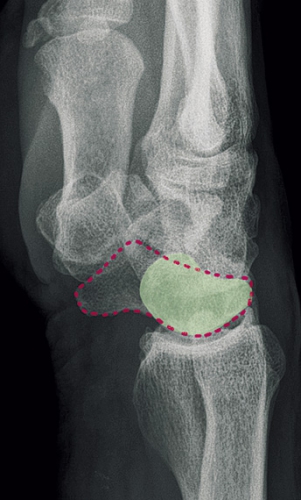

Kliniskt leder denna utveckling till att patienten känner ökad smärta och får nedsatt handstyrka. Karpalbenens patologiska läge och det onormala rörelsemönstret mellan dem leder slutligen till sekundär artros. I detta stadium drabbas patienten även av svullnad, nedsatt rörelseomfång och kontinuerlig värk. Hur lång tid utvecklingen av denna karpala kollaps (scapholunate advanced collapse, SLAC) tar varierar. 10–15 år är en vanlig uppskattning, men i det enskilda fallet med grav ligamentskada och uttalad felställning kan det gå betydligt snabbare. SLAC-utvecklingen följer alltid samma mönster och indelas i stadier enligt Watson:

• Grad I: Artros, osteofytär pålagring vid radiala styloiden

• Grad II: Artros mellan radius och scaphoideum (hela scaphoideum-fasetten av radius)

• Grad III: Artros även midkarpalt (capitatum–lunatum, scaphoideum–capitatum)

• Grad IV: Panartros.

Observera att leden mellan lunatum och radius i princip aldrig är påverkad. SLAC-handled är orsaken till över 70 procent av alla fall av handledsartros [2].